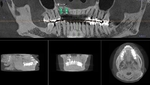

CT Scanner for Optimal Treatment Planning

New iCAT CT scanner offers precise imaging with radiation comparable to traditional x-ray units.  Using this 3D imaging technology the doctor can accurately plan surgery, avoid complications, and create custom implant treament plans.

The CT scanner's imaging allows us to create custom made surgical guides specific to each patient.  These surgical guides allow the precise placement of dental implants for optimal functional and esthetic results.

A Case with a Fractured Central Incisor